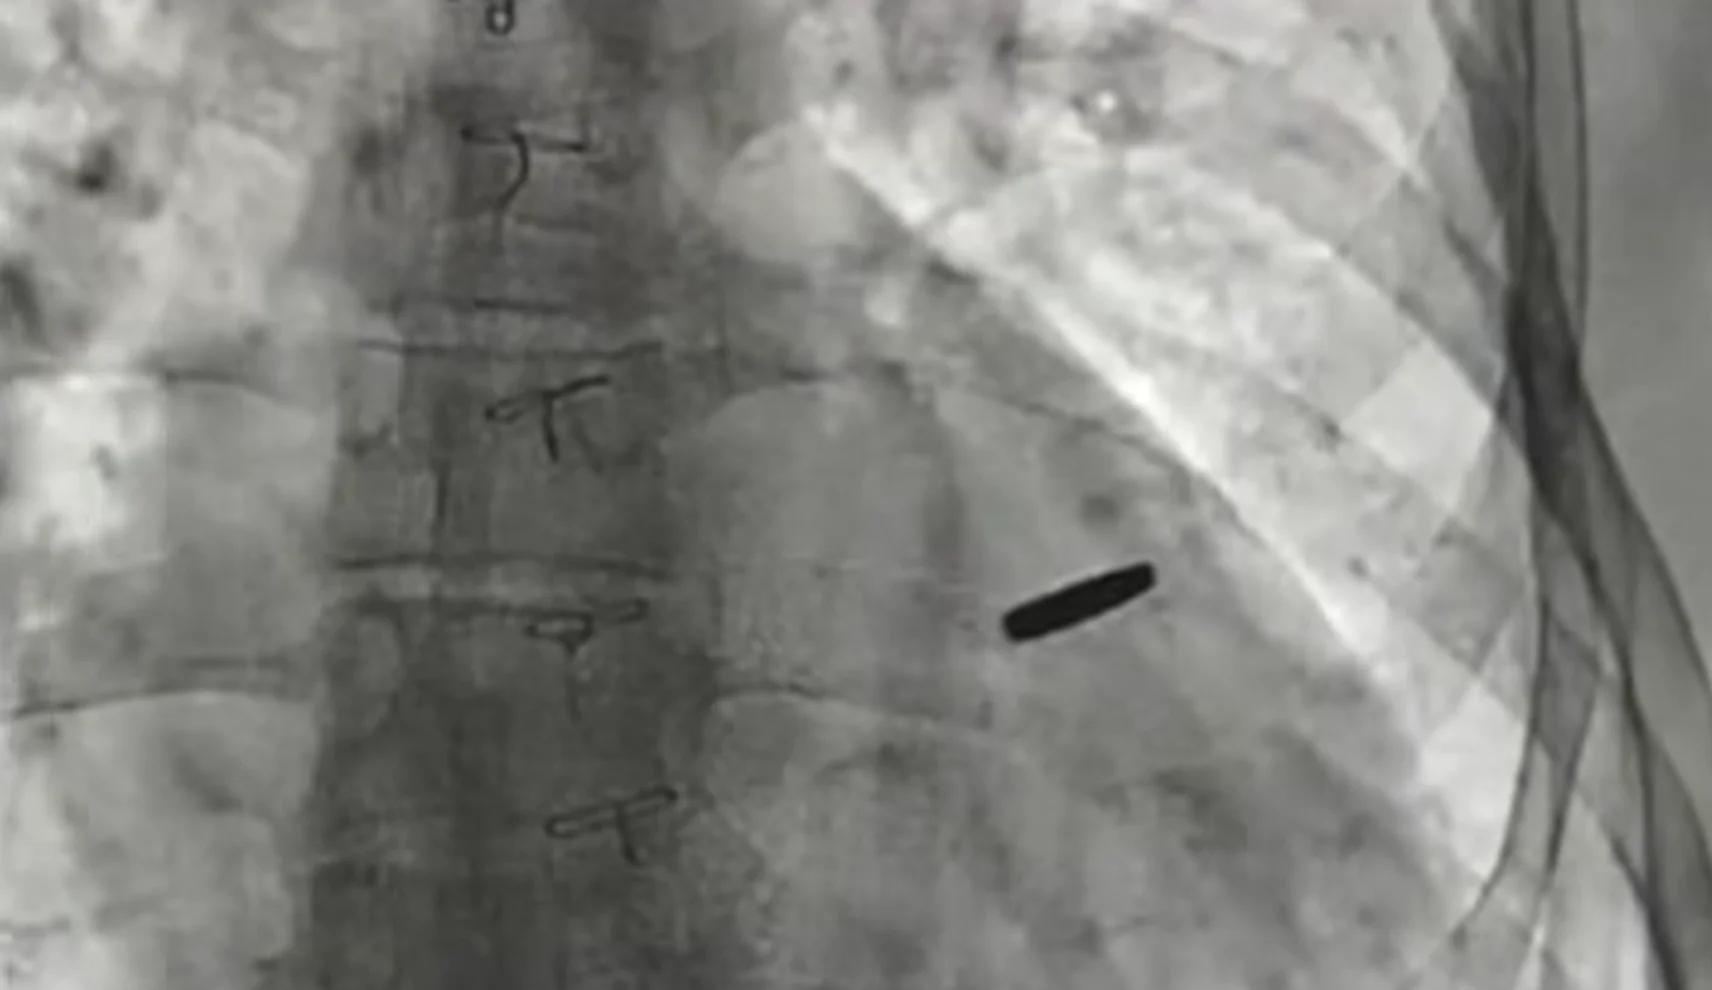

The bullet did not damage major structures and remained shallow. Surgeons operated in less than an hour without stopping the heart, extracting the fragment using a special magnet.

“Serhiy defended Azovstal, lived 3.5 years in captivity with a bullet in his heart. On the third day after its removal, he is already walking in the courtyard of the Heart Institute. Thanks to everyone who supports and frees our guys from captivity. Congratulations to all my colleagues on Surgeon’s Day. Sometimes we manage to create miracles.”